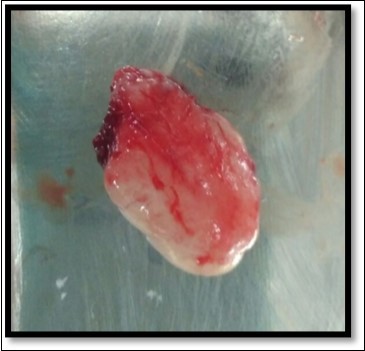

During the next visit local anesthesia was given. The lesion was excised with the help of soft tissue laser and sent for histological examination. (Figure 2) Histological report confirmed the lesion is Peripheral cemento-ossifying Fibroma. Histological analysis showed lesional tissue comprising of both trabecular bone and woven bone. Periphery of the lesion showed numerous globular and irregular cementum like calcification. In most areas these calcification coalesced with each other forming bigger calcification. The supporting connective tissue stroma was loose fibrillar with less cellularity. Detached overlying parakeratinized epithelium was observed in one area. (Figure 3) Post operative evaluation revealed normal healing after one month. (Figure 4)